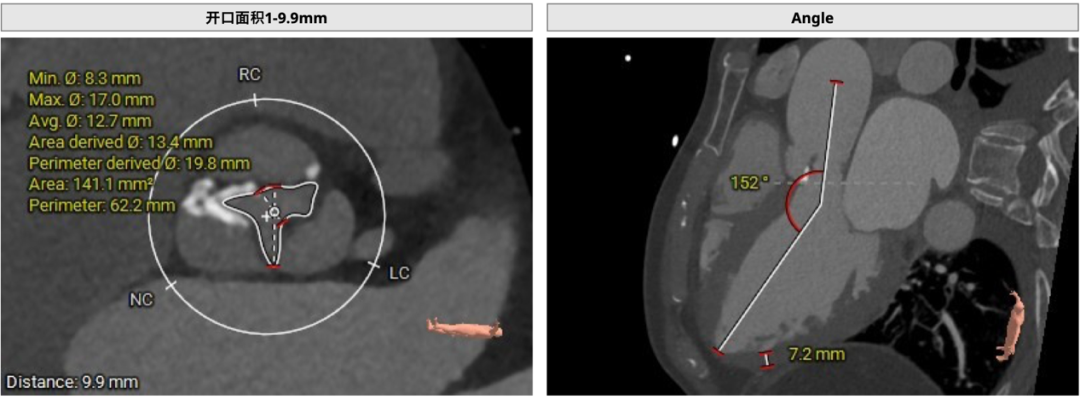

患者主动脉瓣三叶式,瓣叶基本等大,瓣叶增厚,瓣叶游离缘重度钙化,右无瓣叶交界钙化有融合,左右冠瓣钙化至窦底可见。主动脉瓣环周长折算直径约26.1mm:

环上9.9mm开口面积141.1mm²,入路角度152°:

左侧冠脉开口高度低,LCA 9.1mm,左冠瓣瓣叶长度约14.7mm;右侧冠脉开口高度可,RCA 18.7mm: